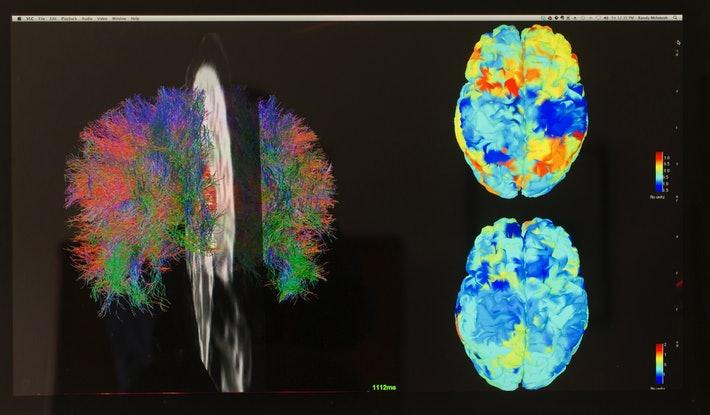

The team wanted to pinpoint the exact mechanism that made the leap from Step 1 to Step 2 — what brought unconscious sensory stimuli to light? To answer this question, they conducted two experiments using brain scans called functional magnetic resonance imaging (fMRI).

An fMRI of a brain. Rick Madonik/Toronto Star/Getty Images